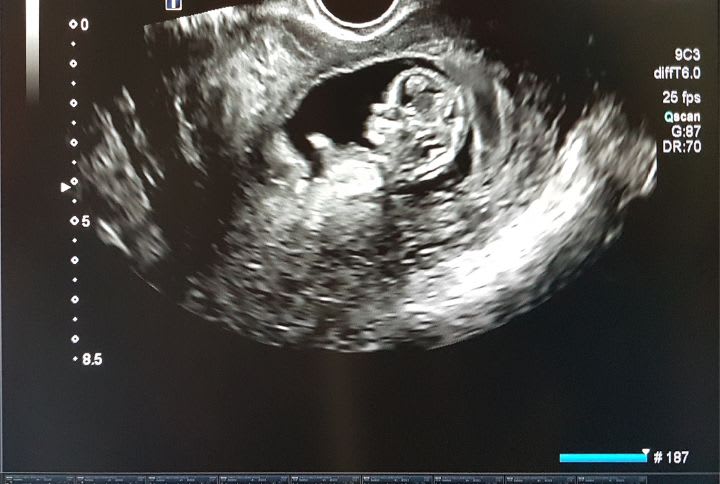

Echographie fœtus

Lors de la première échographie, le praticien mesurera donc l’épaisseur de la nuque du fœtus (clarté nucale) et évaluera son état de santé global.

L’échographie du premier trimestre est un examen essentiel qui dure environ une trentaine de minutes. C’est souvent la première rencontre avec le futur bébé et c’est la première fois que les futurs parents vont avoir l’occasion d’entendre battre le cœur de leur enfant. C’est donc un moment particulièrement émouvant.